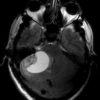

U nguyên bào mạch máu

» Thông tin: Nam giới – 25 tuổi.

» Lâm sàng: Đau đầu + Nôn + Rối loạn thăng bằng.